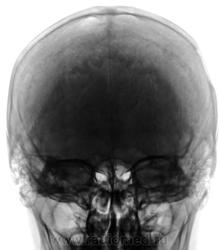

- https://radiomed.ru/sites/default/files/styles/case_slider_image/public/user/12/2.201311050036.jpg?itok=sfVAyZ8C